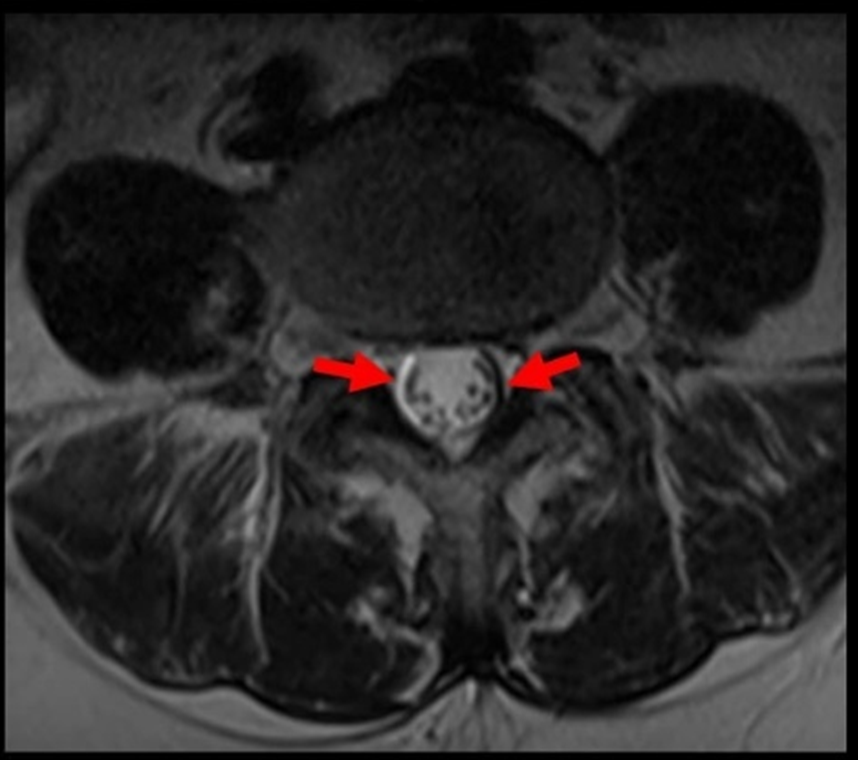

Τα σφάλματα μαγνητικής επιδεκτικότητας είναι ένα συνηθισμένο φαινόμενο στις εξετάσεις μαγνητικής τομογραφίας και δύνανται να εμφανιστούν τόσο στον άξονα κωδικοποίησης...